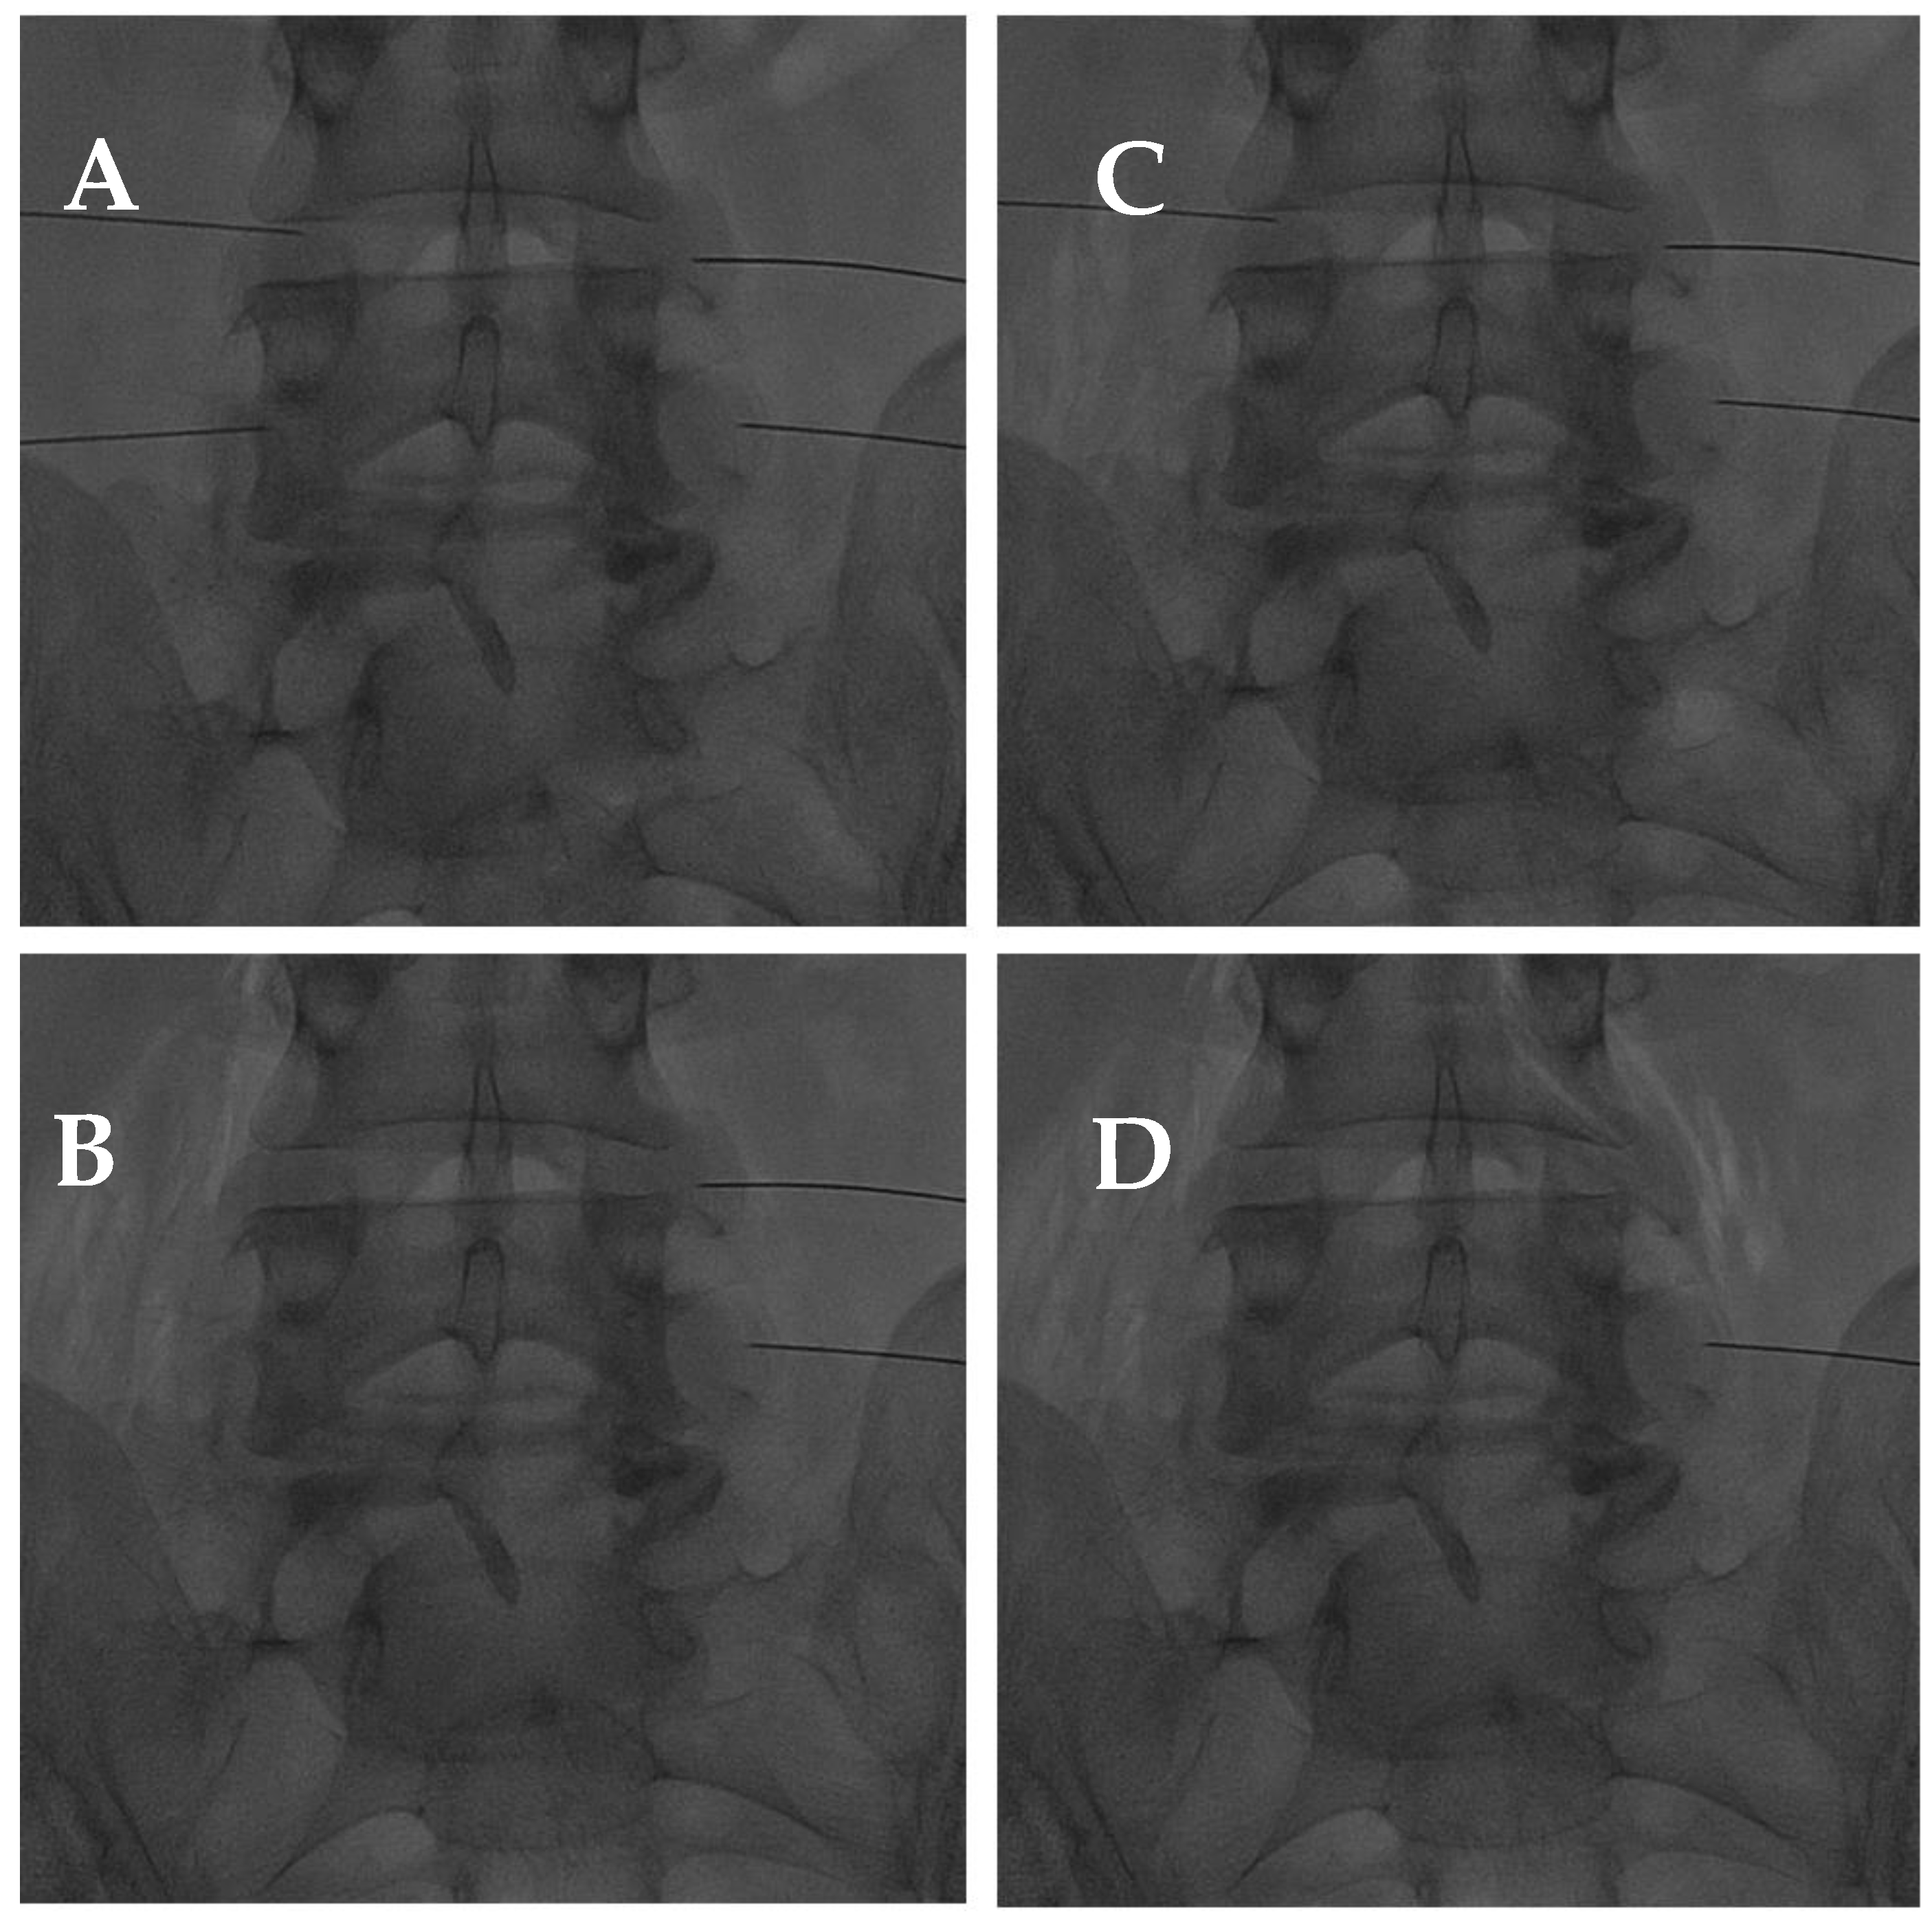

In addition, high levels of ROS have been found in progressed facet joint degeneration since they induce apoptosis pathways, in particular in chondrocyte cells [108]. Hence, in reducing the inflammatory response and oxidative stress, O2-O3 demonstrated good efficacy as anti-antalgic therapy in CLBP, even caused by facet joint syndrome (Figure 10) [60]. Even if the O2-O3 mixture is widely used for these musculoskeletal indications, there is a low level of evidence for its administration, except for CLBP or knee osteoarthritis [102].

Figure 10.

(A) AP fluoroscopic view of four bilateral facet joint puncture; and (B–D) oxygen–ozone mixture intra-articular injection: notice the propagation of oxygen–ozone along the psoas muscle fibers due to pulling the needle back under high pressure.